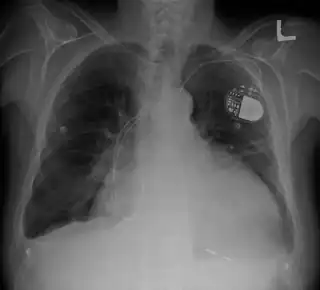

Corazón agrandado en la Rx de tórax.Marcapasos | ||

La cardiomegalia es el término que define un agrandamiento anormal del corazón o hipertrofia cardíaca. Se trata de un signo que aparece en personas con insuficiencia cardíaca sistólica crónica o diversos tipos de miocardiopatías.[1]